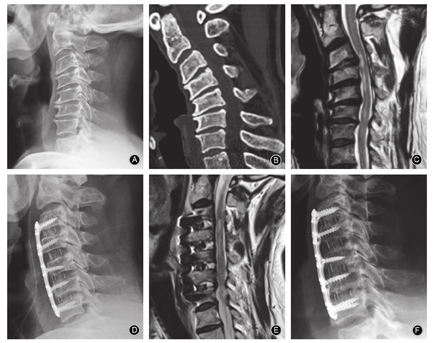

对≥3个节段的脊髓型颈椎病,传统观点认为手术虽然可以直接去除致压物及恢复前凸,但手术风险大、并发症多,如脊髓损伤、脑脊液漏、内植物脱出及假关节形成等并发症发生率高。但随着理念的更新和技术的进展,这种观点正在逐渐被改变。对大部分柔软的颈椎后凸畸形可以行单纯前路手术解决,即使是严重的畸形也能通过前路手术获得满意的矫形[18]。有文献报道对4个节段以前方致压为主的多节段脊髓型颈椎患者行前路手术治疗,获得了良好的临床疗效[19]。另外ACDF治疗脊髓型颈椎病具有显著临床疗效,且颈椎局部矢状位序列保持相对稳定,手术前后颈椎矢状位参数变化与临床疗效具有一定的相关性[20]。因此对致压≥3个节段、脊髓前方受压为主,尤其是合并重度后凸畸形(>40°以上)的多节段脊髓型颈椎病,由于后路椎管成形术后脊髓不能有效后移,可能会影响神经症状的改善。只要不合并连续性长节段后纵韧带骨化或宽基底的后纵韧带骨化、多节段黄韧带肥厚或先天性椎管狭窄,且术者熟练掌握颈椎前方解剖结构、多节段椎间隙减压和固定技术,可以选择前路手术,只是手术时间相对延长,不一定增加并发症的发生率(图3)。术式最好以ACDF或ACDF+ACCF为主,如减压节段较多,或椎体次全切后钛网过长,为防止钛网塌陷,选择混合手术减压方式可达到有效减压、固定及矫形的目的[21]。